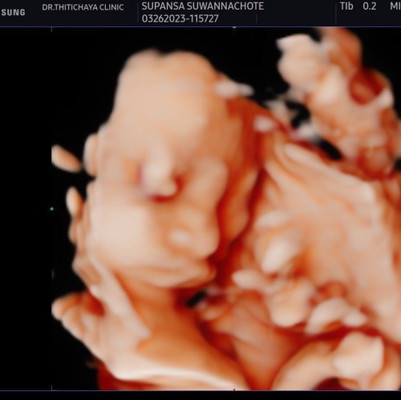

อัลตราซาวด์ซาวด์4มิติ

ในซาวด์ลูกดูจมูกโด่งมาก ผลอัลตราซาวเชื่อได้มากน้อยแค่ไหนคะ แม่ๆคนไหนซาวด์มาแล้วบ้างคิดเห็นอย่างไรกันคะ

ทางนี้ซาวด์ตอน 24 วีค 4 วัน 5 มิติ หวังว่าจะออกมาเหมือนในรูป ลูกสาวค่า

ใช่ค่ะ หมอบอกจมูกโด่งในซาวด์ก็ดูโด่งออกมาไม่รู้จะเป็นเหมือนในซาวด์ไหม